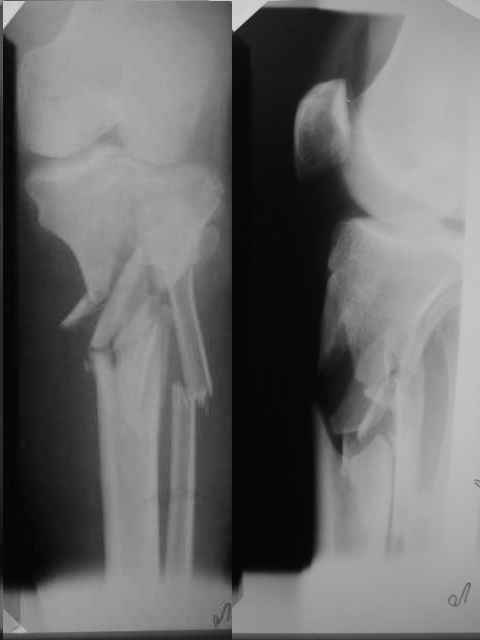

Выполнили операцию "желтому мужчине"(суррогаты так и продолжают пить)! С диагнозом:Перелом костей таза с нарушением тазового кольца

(перелом лонной ,седалищной костей справа .Разрыв КПС слева)Открытый (1 А Каплан) оскольчатый перелом проксимального эпиметафиза большеберцовой кости.

Сделали на 14 сутки остеосинтез б/берцовой кости мыщелковой пластиной LCP, остеосинтез костей таза АВФ(передняя опора, извинямси за качество R-грамм). Сохраняется смещение. Попытаемся его устранить этапно, но сомневаемся хватит ли жесткости АВФ и нет нигде меодики введения илиосакральных винтов!